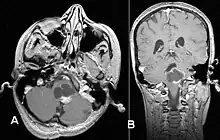

Usually – depending on the interview of the patient and after a clinical exam which includes a neurological exam and an ophthalmological exam – a CT scan and/or an MRI scan will be performed to confirm the presence of a tumor. They are usually easily distinguishable from normal brain structures using these imaging techniques. A special dye may be injected into a vein before these scans to provide contrast and make tumors easier to identify. Pilocytic astrocytomas are typically clearly visible on such scans, but it is often difficult to say based on imaging alone what type of tumor is present.

Pilocytic astrocytomas are often cystic tumors, and, if solid, tend to be well-circumscribed.